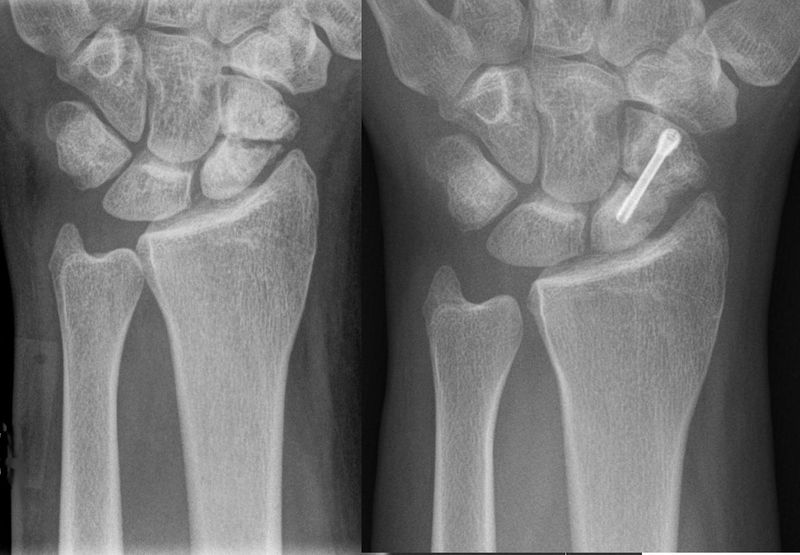

File:Scaphoid-Pseudarthrose1.jpg

"Scaphoid-Pseudarthrose1" by Hellerhoff - Own work. Licensed under CC BY-SA 3.0 via Wikimedia Commons - https://commons.wikimedia.org/wiki/File:Scaphoid-Pseudarthrose1.jpg#mediaviewer/File:Scaphoid-Pseudarthrose1.jpg